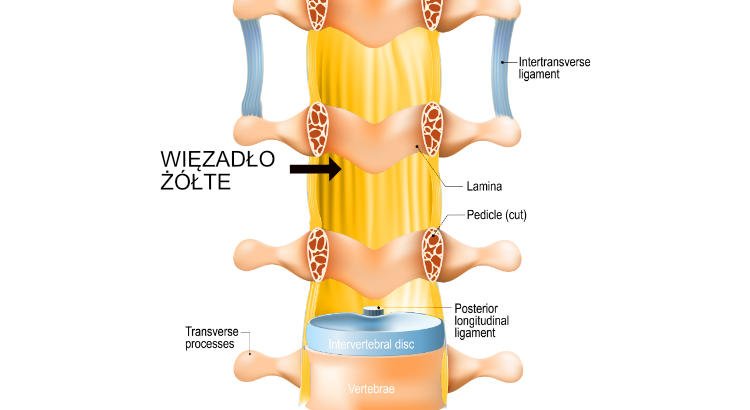

Co to są więzadła żółte?

Więzadła żółte to ważne elementy budowy kręgosłupa. to sprężyste pasma w kręgosłupie, które tworzą tylno boczne ściany kanału kręgowego. Przyczepiają się do kości kręgów tworząc zwarte zasłony. Ich zadaniem jest również nadawanie kręgosłupowi elastyczności. Ich grubość rośnie wraz w oddalaniem się od głowy. Najcieńsze są w odcinku piersiowym, a najgrubsze w odcinku lędźwiowym. Po angielsku i łacinie pojedyncze więzadło żółte kręgosłupa nazywa się ligamentum flavum, a w liczbie mnogiej ligamenta flava.

Normalne więzadła żółte w tomografii komputerowej

Normalne więzadła żółte w rezonansie magnetycznym